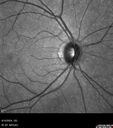

Normal IR 109 views